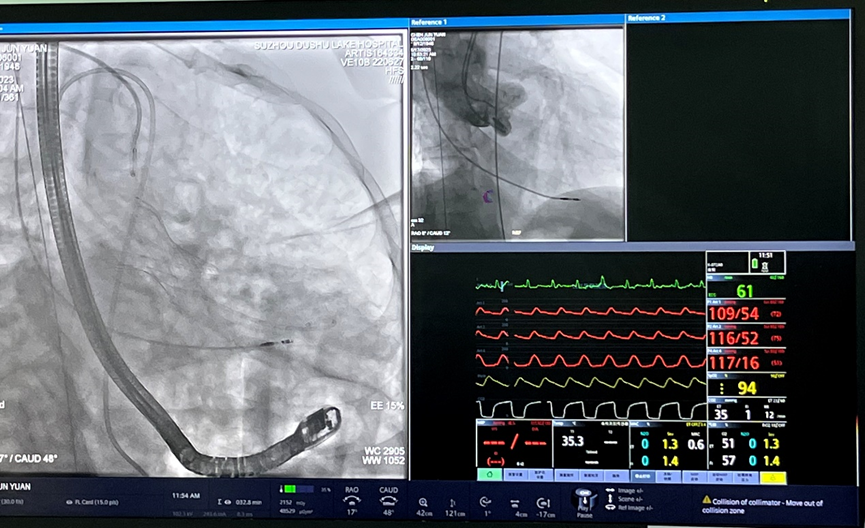

5月17日上午,在多学科协作诊疗(MDT)团队的倾力协助及全体医护人员的共同努力下,苏州市独墅湖医院(苏州大学附属独墅湖医院)心血管内科周亚峰教授团队成功地为一名“Type 0型”主动脉瓣二叶畸形合并重度狭窄患者完成了经导管主动脉瓣置换术(以下简称“TAVR”),手术顺利,术后效果显著。此次手术使用的经导管主动脉瓣膜系统,为前沿独特创新技术,不仅帮助患者解除了困扰多年的病痛,同时也体现了我院心内科在处理复杂病例方面较高的技术水平和丰富的经验,标志着我院在高难度微创心血管介入领域取得突破性进展。

患者为74岁男性,因“反复胸闷1年余,加重1周”入住我院心内科病房。入院后完善心脏彩超,根据结果诊断为主动脉瓣重度狭窄。此次手术选用园区某生物医药公司自研的瓣膜,术前跨瓣压差测得68mmHg左右,术后即刻跨瓣压差小于5mmHg,手术效果较好。